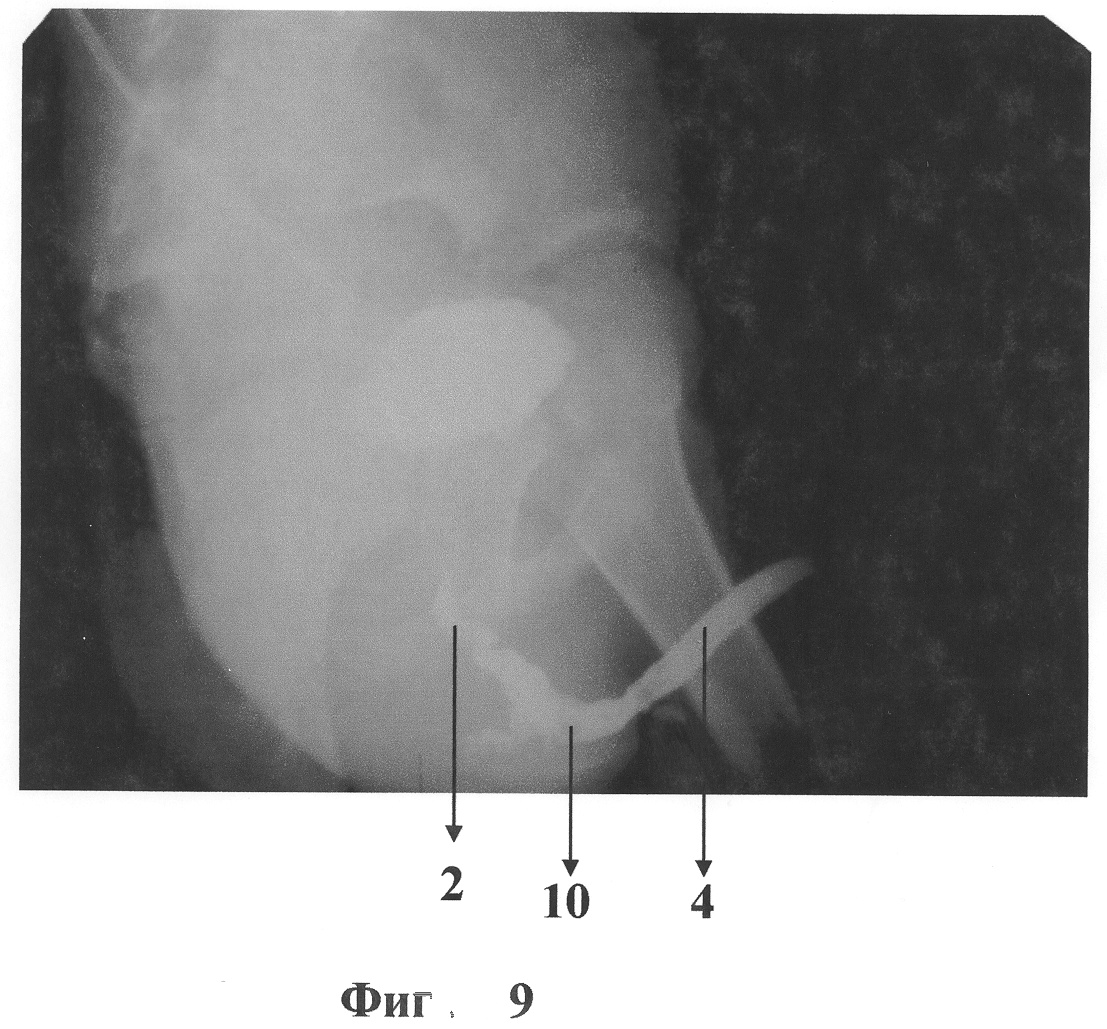

Естественное отверстие в диафрагме таза, через которое проходит уретра, и наружный сфинктер мочевого пузыря тупо расширяют. Через образовавшийся тоннель заводят лоскут мочевого пузыря. Для этого лоскут откидывают и проводят свободно вниз без ротации и значительного натяжения. Таким образом, проксимальный отдел уретры расположен после выведения лоскута на промежность кзади от лоскута, слизистая часть трансплантата, из которой будет сформирована трубка и последующие анастомозы, обращена кпереди. Фиг.5. Для того чтобы произвести транспозицию, в бесслизистой части лоскута на уровне нижнего края предстательной железы, тупо выполняют отверстие, фиг.5 указатель 9, через которое проксимальную уретру выводят на переднюю поверхность лоскута. Фиг.6. Мышечный массив лоскута, обхватывающий уретру после транспозиции, фиксируют швами к прилежащим мышцам промежности во избежание сдавливания мочеиспускательного канала в последующем при акте мочеиспускания. Из мочевого пузыря через проксимальный отдел уретры заводят стент, на котором из слизистой части лоскута формируют трубку. Фиг.7 указатель 10. После чего стент проводят через дистальный отдел уретры и выводят через меатальное отверстие пениса. Стент остается на 7-10 дней после операции.

Накладывают косые анастомозы между сформированной трубкой и дистальным и проксимальным отделами уретры. Фиг.8, фиг.9. Целостность мышц и кожи промежностного разреза восстанавливают. Из срединного разреза выполняют эпицистостомию, а дефект мочевого пузыря, образовавшийся после забора лоскута, ушивают до эпицистостомы. Часть симфиза после остеотомии возвращают на место и фиксируют швом или спицей в зависимости от возраста. Целостность надкостницы восстанавливают. Нижнесрединный разрез послойно ушивают до дренажа.

Выполнена транспозиция лоскута и уретры: для этого в бесслизистой части лоскута на уровне предстательной железы тупо проделано отверстие, через которое заведен проксимальный отдел уретры. После этого уретральная трубка сформирована из слизистой части лоскута, наложен косой проксимальный уретро-уретроанастомоз на стенте. Далее вновь сформированная уретра доведена до дистального отдела. Наложен косой дистальный уретро-уретроанастомоз. Детрузорная часть лоскута фиксирована к мышцам промежности. Тазовое кольцо восстановлено. Мочевой пузырь ушит с оставлением стомы. Выполнена тампонада переднепузырного венозного сплетения гемостатической губкой. Фрагмент симфиза возвращен на место, надкостница ушита узловыми швами. Дренаж через контрапертуру в правой пахово-подвздошной области в паравезикальное пространство. Послойно швы на подкожную клетчатку и кожу.

Стент удален на 10 сутки после операции. Эпицистостома – на 14 сутки.

При выписке: мочеиспускание самостоятельное, мочу держит. Явлений энуреза нет. На снимках уретра проходима. При урофлоуметрии данных за инфравезикальную обструкцию нет. Фиг.9.